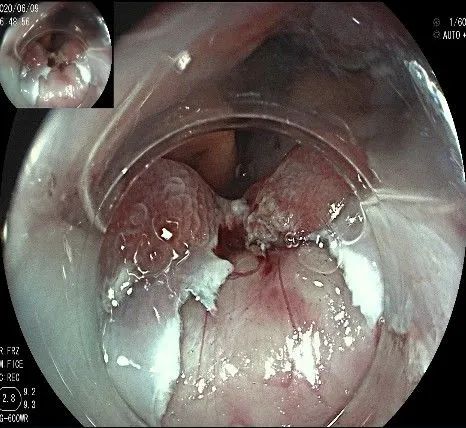

在食管腔内,瘤体的两侧行粘膜下注射后,在瘤体顶部纵向自口侧向肛侧切开食管粘膜。

向下一直切开至齿状线处,白色为鳞状上皮,红色为腺上皮,颗粒样的部分,就是炎性息肉。切开后可见瘤体为白色,表面有血管网,质地较韧。